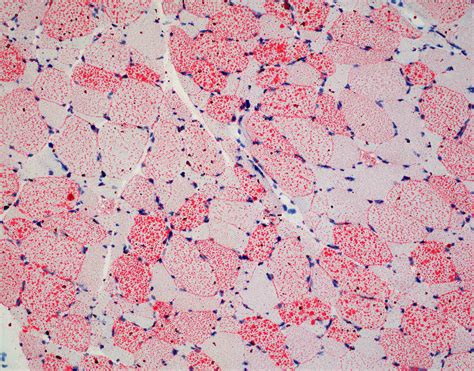

Interpreting Oil Red O Stained Sections

Interpreting Oil Red O stained sections requires careful examination under a microscope. The stained lipids appear bright red, while the background tissue may appear counterstained or unstained, depending on the use of a counterstain. Here are some key points to consider when interpreting the stained sections:

• Lipid droplet size and distribution: The size and distribution of lipid droplets can provide insights into lipid metabolism and storage. For example, large lipid droplets may indicate lipid overload, while small, dispersed droplets may suggest active lipid metabolism.

• Lipid accumulation in specific cell types: The technique allows for the visualization of lipid accumulation in specific cell types, such as adipocytes, hepatocytes, or macrophages. This can help identify the cellular sources of lipid accumulation in various pathological conditions.

• Quantification of lipid content: The intensity of the red stain can be quantified using image analysis software, allowing for the measurement of lipid content in tissues. This is useful for comparing lipid accumulation in different experimental conditions or disease states.

To enhance the interpretability of Oil Red O stained sections, it is recommended to use appropriate controls and positive stains. Controls can include unstained sections or sections stained with a different lipid stain, such as Sudan IV or Nile Red. Positive stains can include sections known to contain high levels of lipids, such as adipose tissue or liver tissue from obese animals.